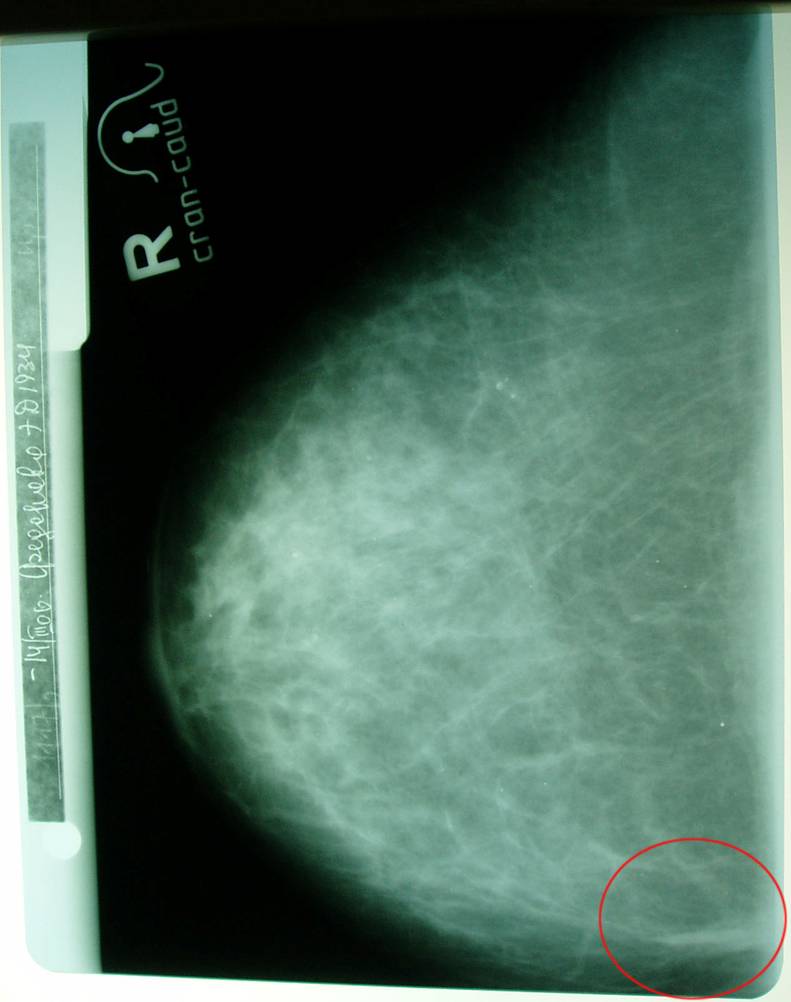

Маммограмма в динамике.

Больная раком правой молочной железы T4аN0M0. Регресс.

11.04.2007 (полтора года лечения и наблюдения)